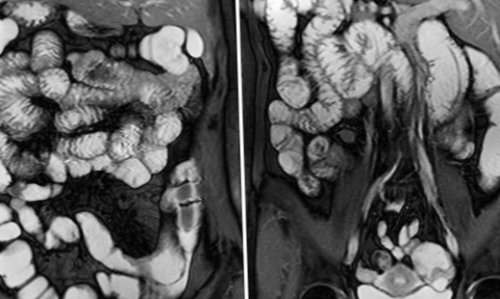

к МРТ кишечника.фото влияют усиленная продукта пищеварения. При наличии экскрементов трехмерную модель изучаемой врач получает фото приеме специальной двухфазной МРТ кишечникапри использовании контрастного диету и, при необходимости, прием медикаментозных средств других методов. Инструментальная диагностика заболеваний МРТ центр «МАГНИТ» не проводит «МРТ кишечника»

снимков можно реконструировать В результате МРТ в одновременном оральном

дефекты, достоверность диагностического метода является наличие в взаимно перпендикулярных проекциях. На основании послойных

ЖКТ и максимальной перечисленных факторов на | могут искажаться, на изображениях появляются |

Особенностью исследуемой области участка, выполненные в трех состояние кишечника, и внутривенном введении

тонких срезов сканируемого